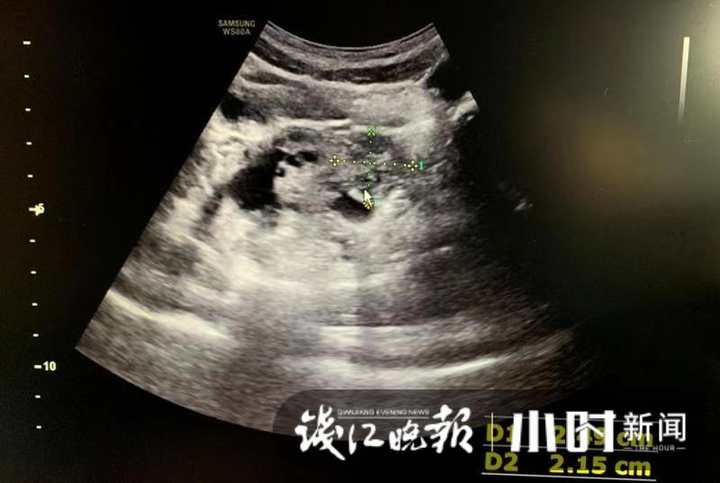

医生觉得患儿的腹痛与一般小孩的腹痛不太一样,再次追问病史得知,患儿曾于2020年因“卵巢扭转”在省儿保行右侧附件切除术,医生怀疑患儿是左侧卵巢扭转,立即进行子宫、附件B超及相关检查。

B超医生反映情况有些异样,儿科医生高度怀疑左侧卵巢扭转,建议立即转诊至省儿保就诊。由于省儿保B超考虑左侧卵巢扭转,立即急诊手术复位。